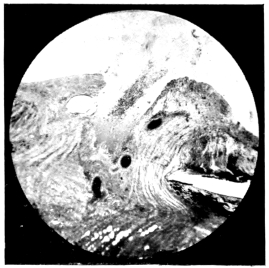

PLATE IV.

22.

LENS DISLOCATED BEHIND RETINA

curly bracket span

48

23.

FISTULA OF THE CORNEA

24.

CAPSULO-CORNEAL SYNECHIA

25.

RETINO-CORNEAL SYNECHIA

26.

SCLERAL FISTULA

27.

"    " (MAGNIFIED)